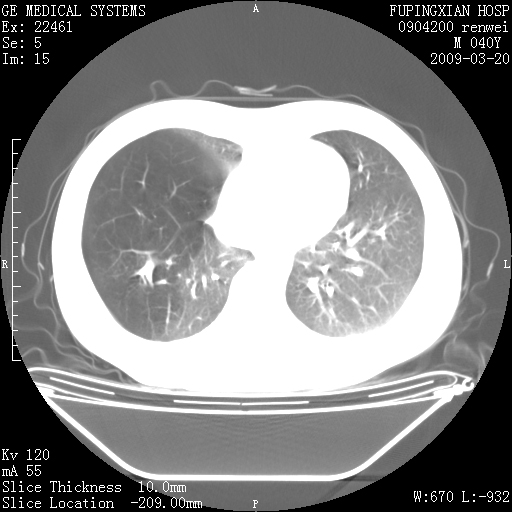

标题: CT18920:平时体健,体检时发现以下问题。

单侧肺气肿表现,原因?   特发性或先天性可能

右肺气肿。

右肺局限性肺气肿

右肺局限性肺气肿。

右肺局限性肺气肿,有无呛咳史?

双肺弥漫磨玻样改变,肺纹理增重,考虑早期间质纤维化伴局部阻塞肺气肿,[考虑黏液栓]

右肺局限性肺气肿;[考虑黏液栓]所致。

双肺弥漫磨玻样改变,右肺局限性肺气肿。病人没有症状?

考虑间质性肺炎伴右侧局限性肺气肿,

先天性支气管闭锁

右肺局限性肺气肿,原因?先天支气管闭锁?粘液栓?